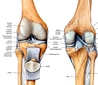

Eklem Sıvısının Özellikleri